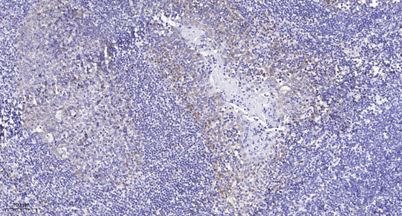

Immunohistochemical analysis of paraffin-embedded human tonsil. 1, Antibody was diluted at 1:200(4 overnight). 2, Tris-EDTA,pH9.0 was used for antigen retrieval. 3,Secondary antibody was diluted at 1:200(room temperature, 45min).